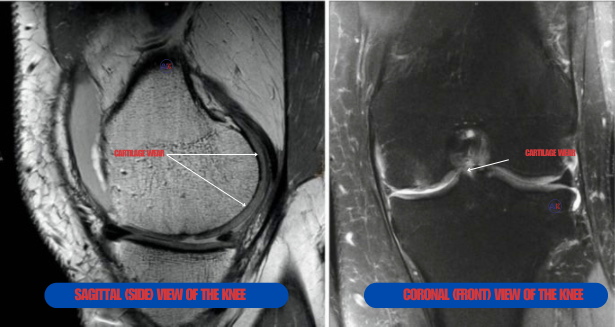

Diagnosis of knee cartilage injuries involves a combination of methods:

- Imaging Tests: X-rays to rule out bone fractures, MRI scans to visualize cartilage damage, and sometimes CT scans for more detailed bone and soft tissue assessment.